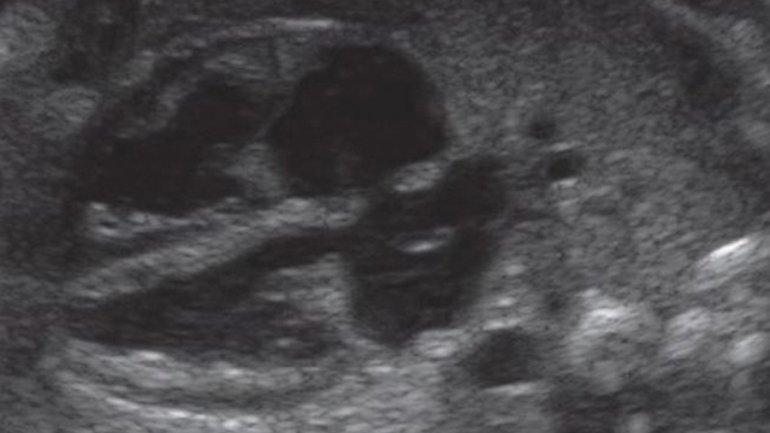

Ultraschall 12. SSW

Auf dem Ultraschallbild sieht man den Kopf und einen Teil des Oberkörpers. Im Kopf sieht man die Schädelknochen und die Anlagen von Kiefer und Zähnen, im Oberkörper den Knochen des Schlüsselbeins. Auch die kleine Nase und der Mund sind gut zu erkennen – und das, obwohl der Fötus nur fünf Zentimeter misst.